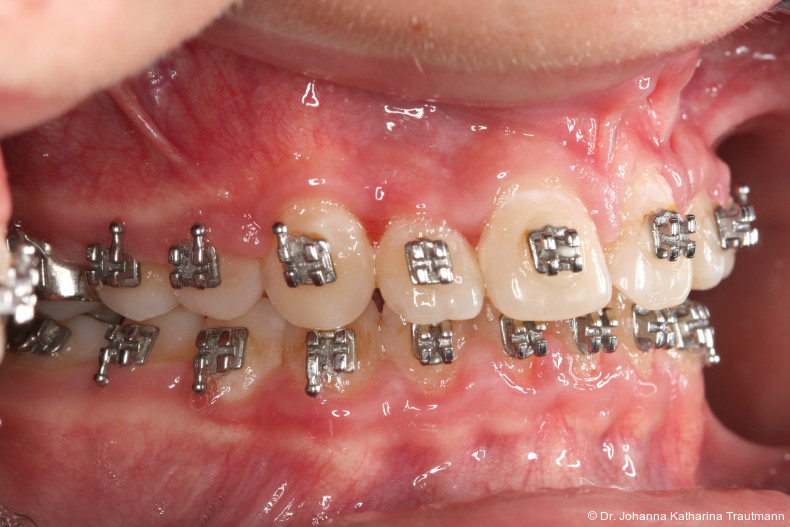

Nach etwa zwei Jahren initialer Behandlung konnte nach abgeschlossenem Wurzelwachstum aller bleibenden Zähne (mit Ausnahme der Weisheitszähne) mit der Hauptbehandlung unter Verwendung einer vollständigen Multibracketapparatur von 7 bis 7 im Ober und Unterkiefer begonnen werden. Die vergleichsweise lange Vorbehandlung erscheint zwar auf den ersten Blick behandlungszeitverlängernd, sorgt jedoch für eine deutlich bessere Mundhygienefähigkeit sowie für eine Reduktion des apparativen Aufwandes und der biomechanischen Komplexität in der Hauptbehandlungsphase. Diese Faktoren stehen in engem Zusammenhang mit Patientenkomfort und Motivation.

Studien zeigen, dass insbesondere Schmerzsensationen und Unbehagen in den ersten Tagen einer kompletten festsitzenden Apparatur erheblichen Einfluss auf die langfristige Kooperationsbereitschaft haben können.11, 12 Kleinere Teilapparaturen verursachen weniger Diskomfort und erleichtern so den Einstieg in die festsitzende Therapie.

Im Rahmen der Multibrackettherapie wurde bewusst der Zahn 13 aus dem Hauptnivellie rungsbogen ausgelassen, um Kippungen und Asymmetrien im Zahnbogen zu vermeiden. Der Zahn 23 wurde locker mit einer Distanz ligatur angebunden, um eine weitere Bewegung nach vestibulär zu erreichen. Auf einem 0.019" x 0.025" Stahlbogen erfolgte anschlie ßend mittels Umgehungsbiegung sowie eines Overlaybogens (0.014" NiTi) die Integration des Zahnes 13 in den Zahnbogen. Die Zwischendiagnostik nach einem Jahr festsitzender Behandlung zeigte eine gelungene Bisshebung bei guter Nivellierung des Okklusionsplanums und orthoaxialer Einstellung der Frontzähne. Die Zahnbögen präsentierten sich harmonisch ausgeformt, es zeigte sich jedoch eine verbleibende Torqueproblematik an bei den Oberkiefereckzähnen. Nach Freilegung und Einstellung verlagerter Eckzähne ist eine korrekte Torque und Angulationssteuerung häufig eine Herausforderung. Während vestibulär verlagerte Zähne zu gingivalen Rezessionen neigen, behalten palatinal verlagerte Zähne oft ihre palatinale Wurzelstellung bei.13, 14 Die genutzte MBTPrescription der Brackets bietet die Möglichkeit, zwischen +7°, 0° und –7° Torque zu wählen.15 In einem 0.022" System ist bei Verwendung eines 0.019" x 0.025" Bogens jedoch mit einem Torqueverlust von etwa 10° zu rechnen.16